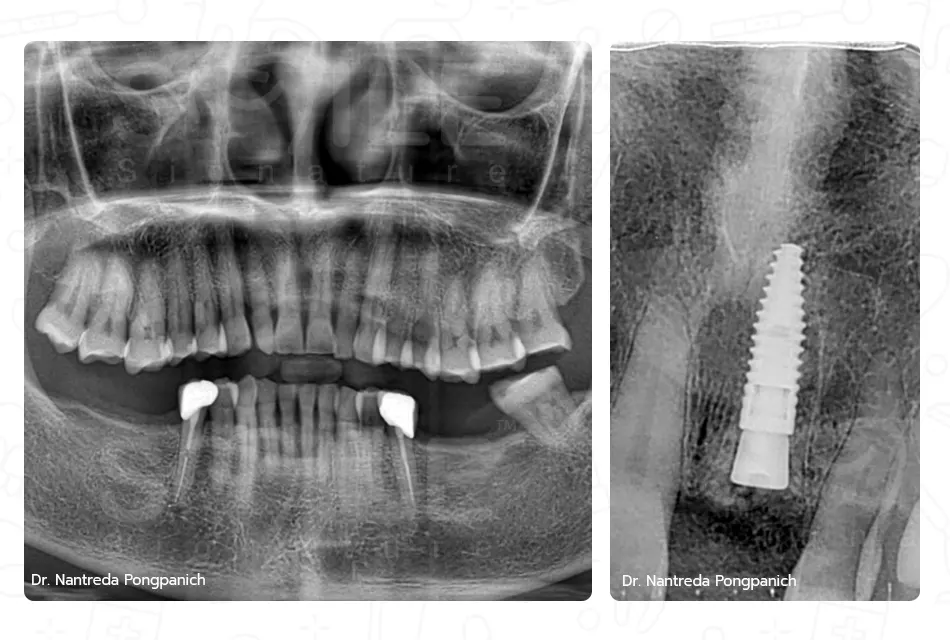

เฉพาะทางสาขาสาขาทันตกรรมรากเทียม, สาขาศัลยศาสตร์ช่องปาก และแม็กซิลโลเฟเชียล